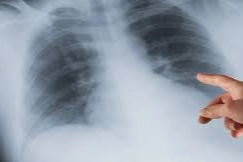

10. Uluslararası Katılımlı Akciğer Sağlığı Kongresi (UASK), 9-12 Nisan tarihlerinde Akciğer Sağlığı ve Yoğun Bakım Derneği'nce (ASYOD) Antalya'da gerçekleştirildi. Kongrede, solunum yolu hastalıklarından tütün bağımlılığına, akciğer kanserinden yapay zekâ destekli tanı yöntemlerine kadar birçok başlık ele alındı. Kongreye katılan Göğüs Hastalıkları Uzmanı Dr. Murat Kıyrık, Türkiye'de akciğer kanserine bağlı ölümlerin ciddiyetine dikkat çekti. Kıyrık, "Akciğer kanserinin Türkiye'de önemli bir sağlık problemi olduğunu düşünüyoruz. Yılda 40 bin kişiyi biz bu hastalıktan kaybediyoruz. Covid'den kaybettiğimiz hastaların 100 bin civarında olduğunu varsayarsak, 3 yılda kaybettiğimizi ancak Covid'de kaybettik. Her yıl 40 bin insanımızı akciğer kanserinden kaybetmeye devam etmemeliyiz" ifadelerini kullandı. "Temel neden sigara ve tütün ürünleri" Akciğer kanserinin etiyolojisinde en önemli faktörün sigara olduğunu vurgulayan Uzm. Dr. Kıyrık, "Hastalarımızın yüzde 90'ı sigara içicisi. Bu noktada sadece sigarayı değil, elektronik sigara, nargile, puro ve pipo gibi diğer tütün ürünlerini de değerlendirmek gerekiyor" dedi. Kıyrık, sigaranın yanı sıra bazı mesleki maruziyetlerin de risk oluşturduğunu kaydederek, "Tozlu işlerde çalışanlar, asbest maruziyeti olanlar, İç Anadolu, Doğu ve Güneydoğu Anadolu'da yaşayanlar risk altında. Köy yaşamı, tandırda yemek pişirme, fırında ekmek yapımı gibi alışkanlıklar da özellikle kadınlarda sigara içmeseler dahi riski artırabiliyor" şeklinde konuştu. "50-80 yaş arası tarama programına alınmalı" Akciğer kanseri görülme yaşının genellikle 50 ile 80 arasında olduğuna işaret eden Kıyrık, "20 yıl boyunca sigara içmiş bir kişi 50-80 yaş arasındaysa bu bireylere mutlaka tarama öneriyoruz. Erken teşhis, hastalıktan kurtulma şansı sunarken; ileri evrede tanı, maalesef genç yaşta kayıplarla sonuçlanabiliyor" uyarısında bulundu. Kıyrık, Sağlık Bakanlığı nezdinde bu konuda girişimlerin sürdüğünü belirterek, "İnsanlarımız, nasıl arabayı 10-15 bin kilometrede bakıma götürüyorsa, kendilerini de belli bir yaştan sonra akciğer kanseri taramasından geçirmeliler. Özellikle ailesinde kanser geçmişi olanlar daha büyük risk taşıyor. Bu nedenle taramanın bir yaşam biçimi haline gelmesi gerekiyor" ifadelerine yer verdi. "11 yaşında sigaraya başlayan biri, 20 yıl sonra akciğer kanseriyle karşı karşıya kalabiliyor" Türkiye'de sigaraya başlama yaşının 11'e kadar düştüğünü belirten Kıyrık, erken yaşta sigara kullanımının büyük risk taşıdığını vurguladı. Kıyrık, "11 yaşında sigaraya başlayan biri, 20 yıl sonra 30'lu yaşlarında akciğer kanseriyle karşı karşıya kalabiliyor. Üstelik sigara miktarı da önemli; günde bir paketle başlamakla birkaç dal içmek arasında büyük fark var" şeklinde konuştu. Ailevi risklere de dikkat çeken Kıyrık, "Babası akciğer kanseri olan hastalarımız var, oğlu da akciğer kanseri oluyor. Baba-oğul birlikte hastalığı yaşıyorlar. Kimi zaman bu kişiler hayatta kalıyor, kimi zaman da maalesef kaybediyoruz. Bunlar oldukça üzücü tablolar" ifadelerini kullandı.